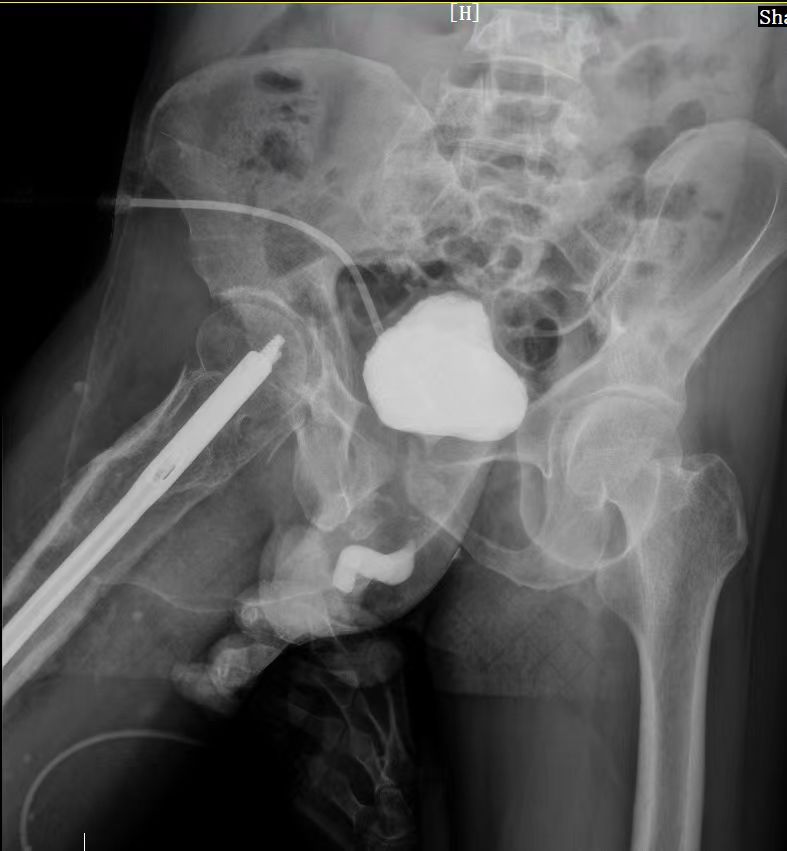

西咸院区移植泌尿外科。经科室大讨论,科室主任李智斌团队迅速制定治疗策略,行尿道造影检查可见尿道完全断裂,遂决定行尿道重建术+尿道狭窄瘢痕切除术。

术中探查发现患者尿道球部完全闭锁,狭窄段长约2cm。要在狭小空间里完成修剪、吻合,难度非常大,对手术技巧要求也非常高。此外,术中还发现患者的尿道闭锁段较长并且瘢痕致密坚硬,难度系数进一步提高。最终,凭借丰富的临床经验,李智斌团队顺利完成了该手术。目前患者已恢复正常排尿,康复出院。